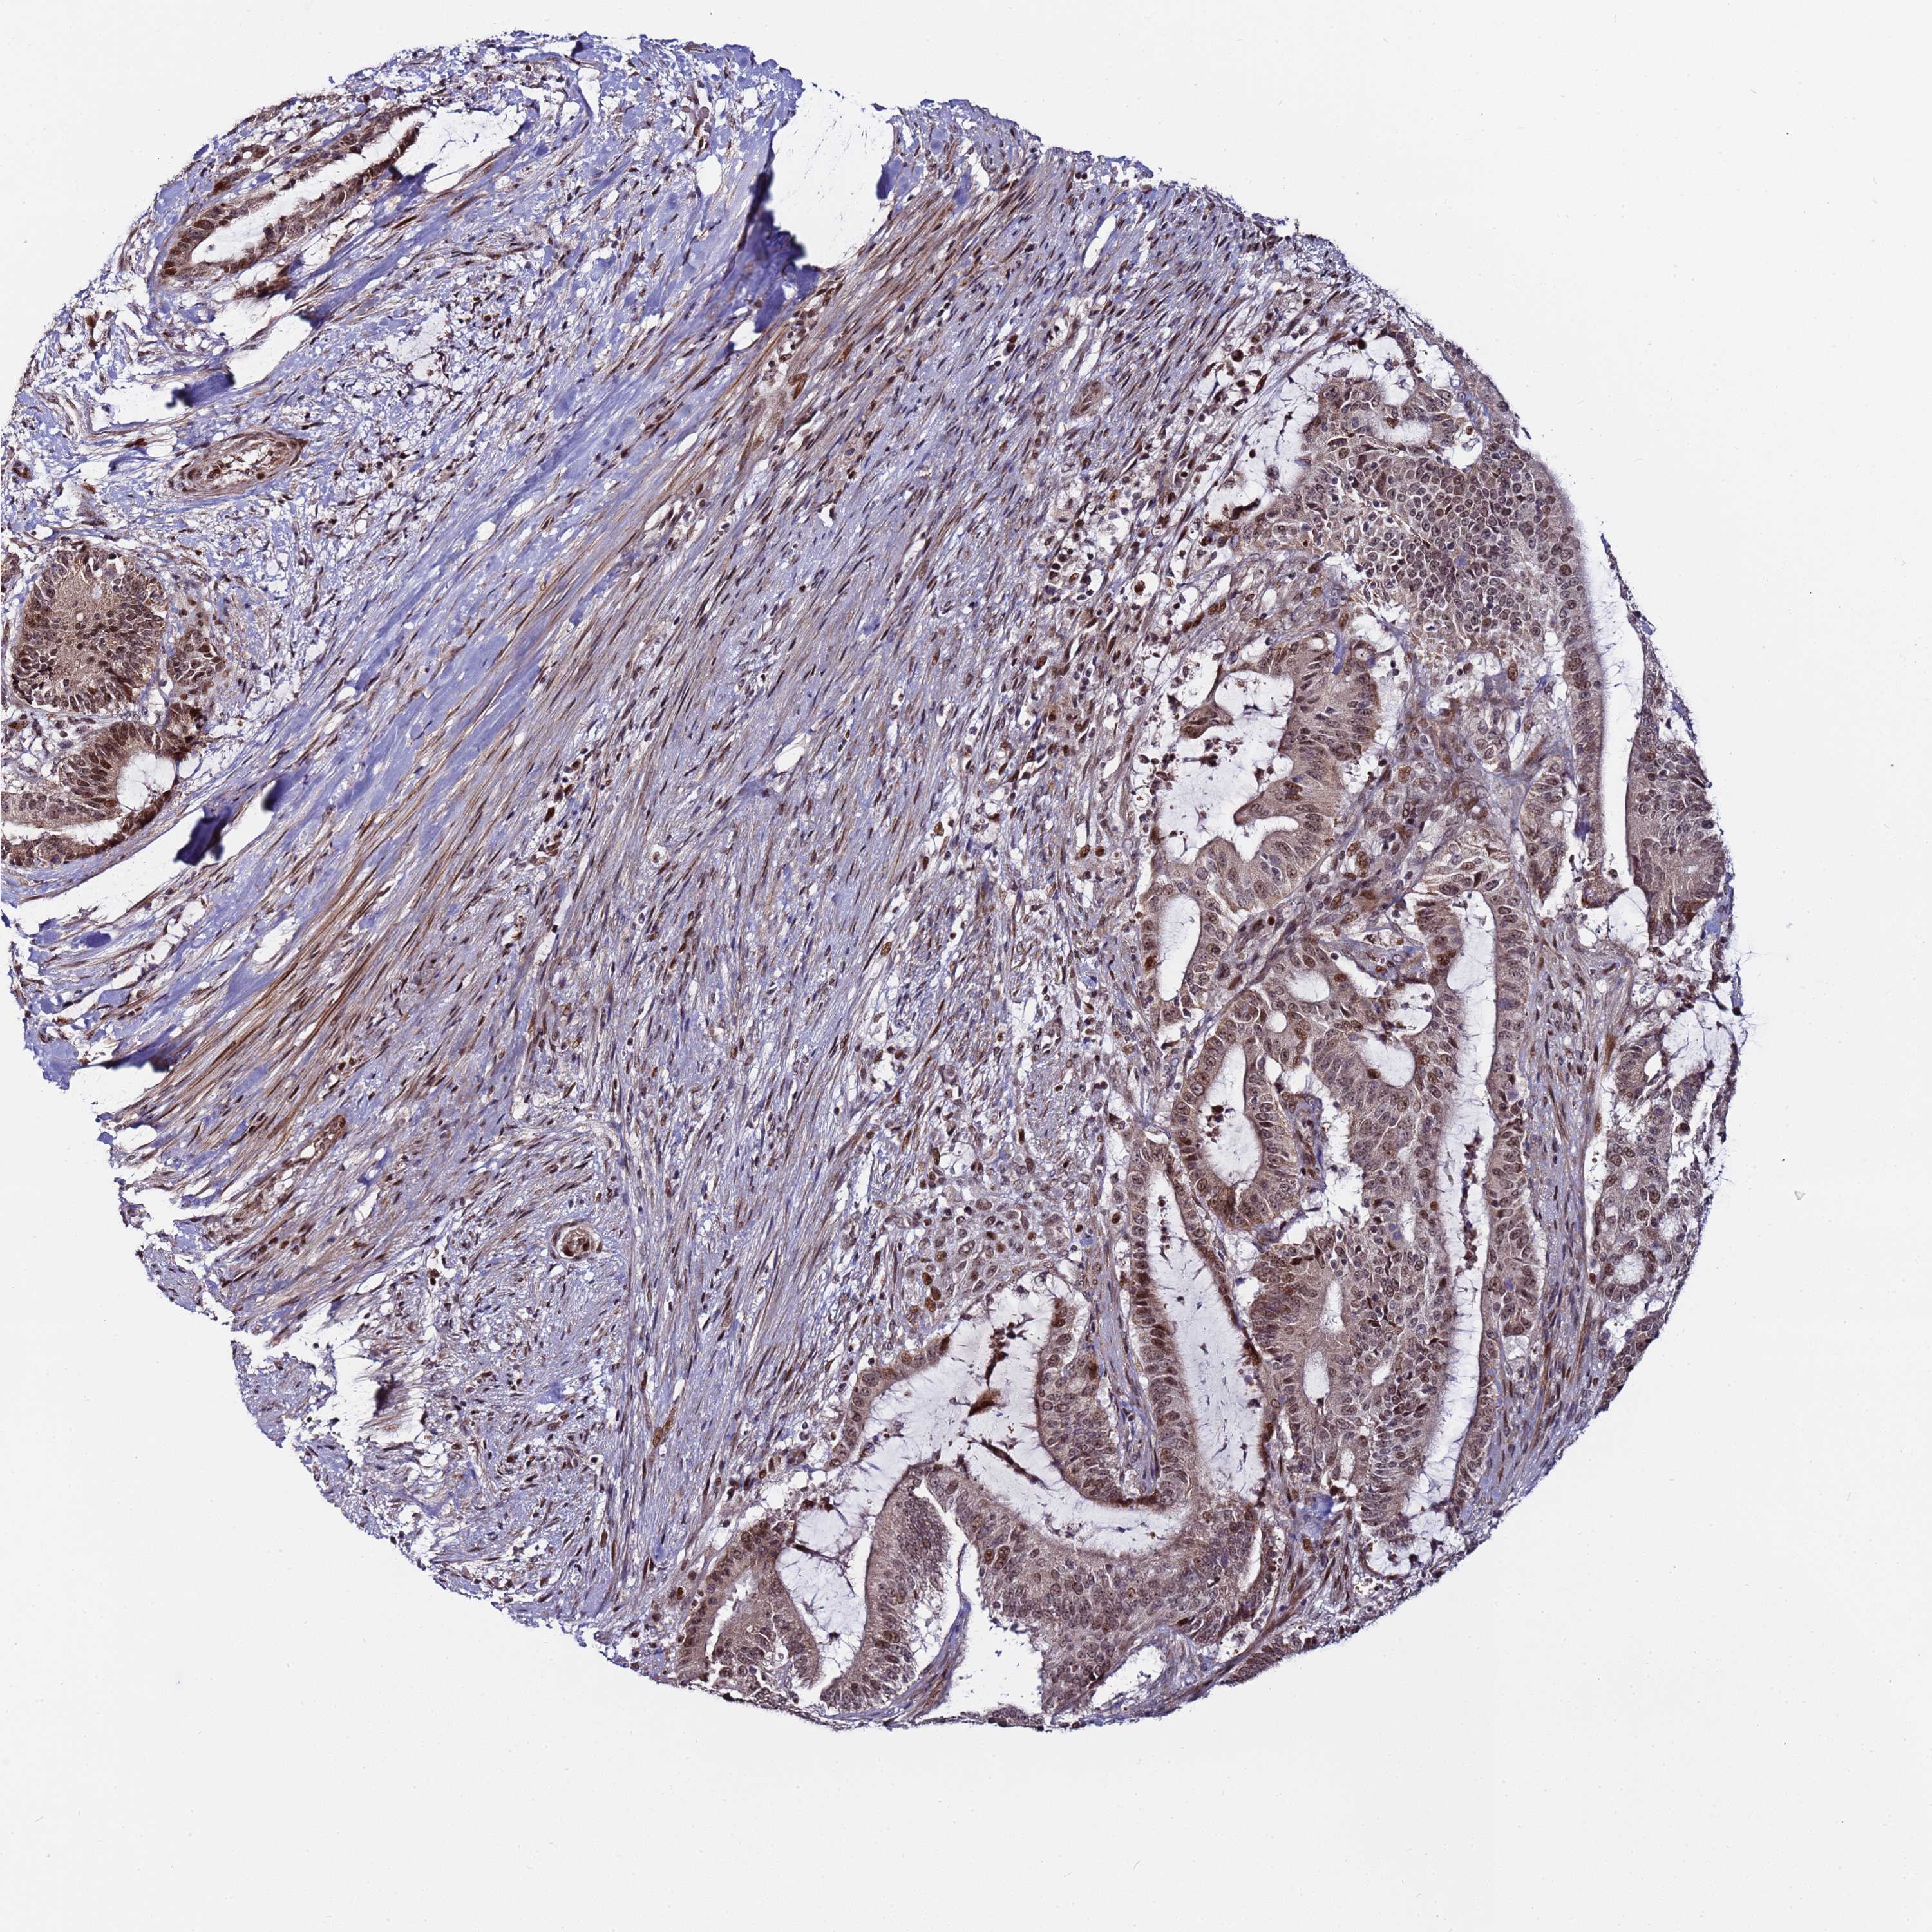

LIVER CANCER - Protein expressioni

A mouse-over function shows sample information and annotation data. Click on an image to view it in a full screen mode. Samples can be filtered based on level of antibody staining by selecting one or several of the following categories: high, medium, low and not detected. The assay and annotation is described here.

Antibody stainingi

Antibody staining in the annotated cell types in the current human tissue is reported as not detected, low, medium, or high, based on conventional immunohistochemistry profiling in selected tissues. This score is based on the combination of the staining intensity and fraction of stained cells.

Each image is clickable and will lead to virtual microscopy that enables deeper exploration of all samples and also displays staining intensity scores, fraction scores and subcellular localization as well as patient and tissue information for each sample.

Antibody HPA044244

Antibody HPA058777

Antibody CAB020694

Staining

High

Medium

Low

Not detected

Intensity

Strong

Moderate

Weak

Negative

Quantity

>75%

75%-25%

<25%

None

Location

Nuclear

Cytoplasmic/membranous

Cytoplasmic/membranous,nuclear

Cholangiocarcinoma

Carcinoma, Hepatocellular, NOS